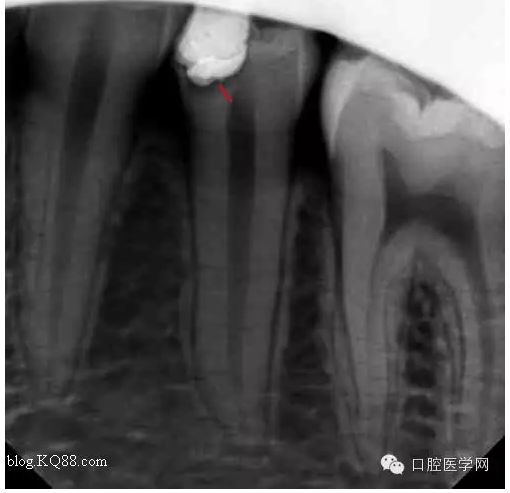

一月后復(fù)查:高聳的髓角變鈍,形成約0.5mm修復(fù)性牙本質(zhì)?;佳罒o癥狀。牙髓活力測試同對照牙。

兩月后復(fù)查:高聳的髓角變的更鈍。遠(yuǎn)中髓壁形成較厚的修復(fù)性牙本質(zhì)。溫度測試同對照牙。